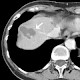

Die beschriebenen unterschiedlichen Temperaturbereiche auf einer Drehanode sind in nebenstehendem Beispiel illustriert.

Brennfleckhub und erhöhte Brennringtemperatur sind gut zu erkennen.

Eingangsparameter für die Berechnung sind

- ein Anodendurchmesser von 100 mm,

- 70 kW Strahlleistung

- in einen elektronischen Brennfleck von 1 mm x 12 mm (Breite x Länge),

- Drehzahl 200 Hz,

- Momentaufnahme nach 10 Umdrehungen (50 ms) nach Belastungsbeginn: